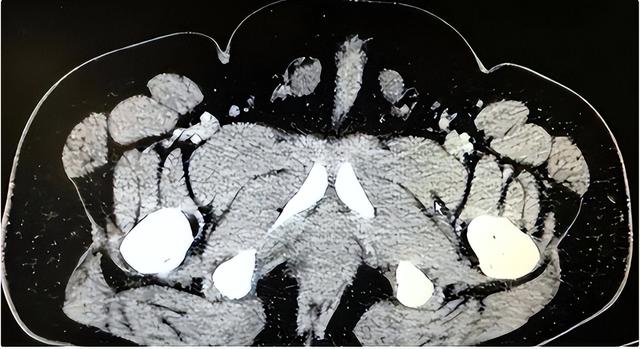

原本他觉得这个问题一辈子都不会得到解答,直到后来有一天他在电视上看到一起科普新闻,看到了双性人的存在。

这一刻他内心压抑的情绪终于爆发了,在跟妻子商量后,他第一次踏进医院去了解自己的情况。

没有想象中的鄙视嘲讽,医生们都非常的专业。

其实双性人虽然少见,但在他之前就已经存在。

并且也有相关的手术可以调整。